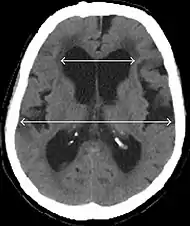

Normal-pressure hydrocephalus (NPH), also called malresorptive hydrocephalus, is a form of communicating hydrocephalus in which excess cerebrospinal fluid (CSF) occurs in the ventricles, and with normal or slightly elevated cerebrospinal fluid pressure. As the fluid builds up, it causes the ventricles to enlarge and the pressure inside the head to increase, compressing surrounding brain tissue and leading to neurological complications. The disease presents in a classic triad of symptoms, which are memory impairment, urinary frequency, and balance problems/gait deviations (note: this diagnosis method is obsolete[1][2]). The disease was first described by Salomón Hakim and Adams in 1965.[3]

Patients with suspected NPH should have typical symptoms in addition to ventricular enlargement on neuroimaging. The international evidenced-based diagnostic criteria for primary NPH are:

- Imaging from magnetic resonance imaging (MRI) or computed tomography (CT) is needed to demonstrate enlarged ventricles and no macroscopic obstruction to cerebrospinal fluid flow. Imaging should show an enlargement to at least one of the temporal horns of lateral ventricles, and impingement against the falx cerebri resulting in a callosal angle ≤ 90° on the coronal view, showing evidence of altered brain water content, or normal active flow (which is referred to as "flow void") at the cerebral aqueduct and fourth ventricle.

MRI scans are the preferred imaging. The distinction between normal and enlarged ventricular size by cerebral atrophy is difficult to ascertain. Up to 80% of cases are unrecognized and untreated due to difficulty of diagnosis.[10] Imaging should also reveal the absence of any cerebral mass lesions or any signs of obstructions. Although all patients with NPH have enlarged ventricles, not all elderly patients with enlarged ventricles have primary NPH. Cerebral atrophy can cause enlarged ventricles, as well, and is referred to as hydrocephalus ex vacuo.